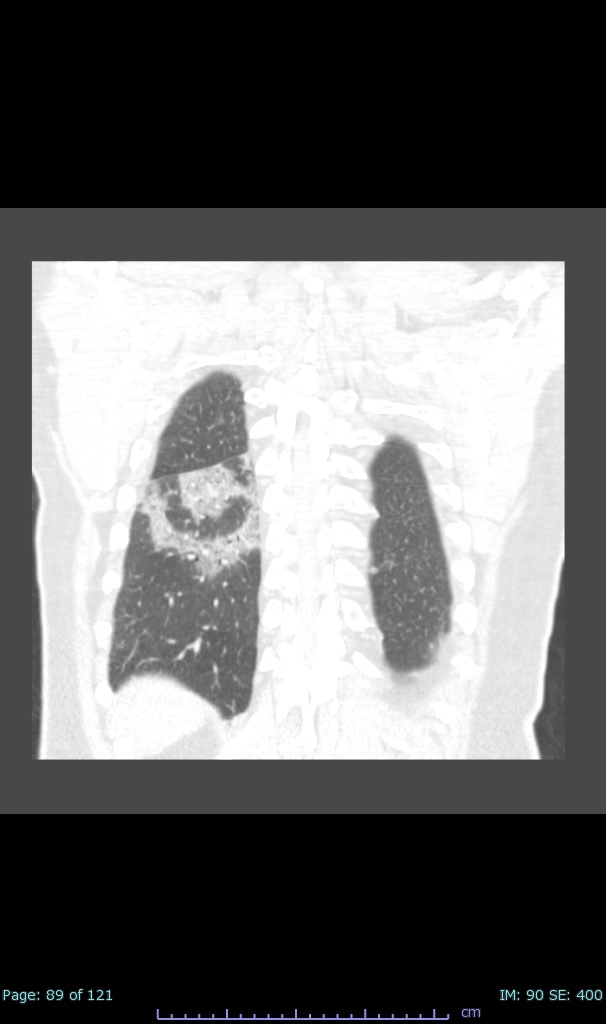

- 100% subpleural involvement, 33% + centrolobular involvement

- 40% even apical/basilar, 27% basilar dom, 5% mid dom. 1/17